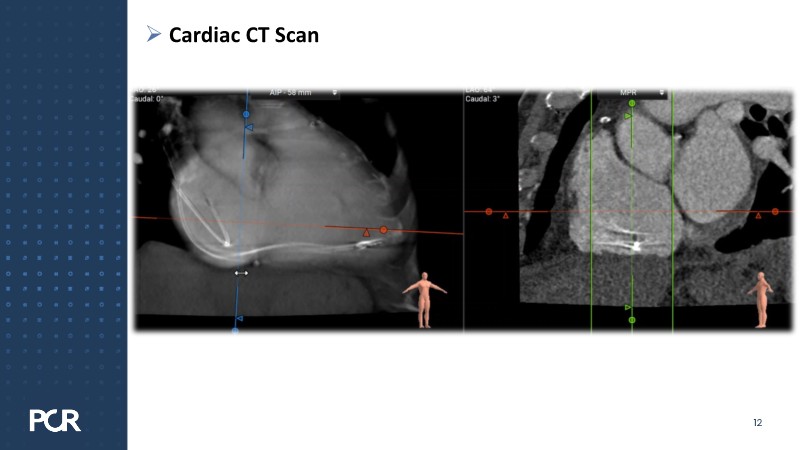

This session addresses emerging topics in structural heart disease by examining patient-centered solutions such as EVOQUE transcatheter tricuspid valve replacement (TTVR) and SAPIEN transcatheter heart valve-in-heart valve (THV-in-THV) procedures. It covers the latest data from Europe on redo TAVI, lifetime management strategies beginning with initial prosthesis planning, evolving patient selection for TTVR, and features an educational live case alongside expert panel discussions on procedure safety and efficacy.

- To understand the latest considerations and techniques for redo TAVI and get exposed to the latest data from Europe

- To learn how to maximise the benefits of TAVI with a lifetime management strategy that starts with the planning of the first prosthesis